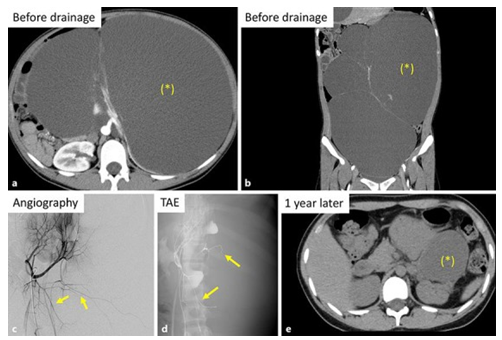

Case 2

In July 2016, a 16-year-old Japanese female was presented with abdominal distension. She had computed tomography (CT) scan of abdomen which demonstrated 4 huge cysts within her left kidney but her right kidney was normal. The total volume of the four cysts was 9,215 mL, and all her kidney cysts were categorized as Bosniak I cysts. (see figures 2a and 2b). Left nephrectomy was recommended in her referring hospital but the patient and her family preferred to avoid nephrectomy and to preserve her left kidney. She had genetic testing including PKD1 and PKD2 which were normal. In view of the fact that intra-cystic haemorrhage had developed in case 1 pursuant to catheter drainage of the kidney cyst, prophylactic TAE was undertaken in the patient so as to avoid bleeding. A total of 8 platinum micro-coils were utilized to block the branches of her left renal artery encompassing the cyst walls (see figures 2c and 2d). Subsequently a total volume of 9,400 mL of cyst fluid was drained from the left kidney cysts. Sclerotherapy was then undertaken through daily infusion of minocycline hydrochloride for 7 days and the catheters were removed. Cytology examination of the cystic fluid was negative for malignancy. During her 1-year post-procedure follow-up the total cyst volume had decreased to 633 mL (see figure 2e).